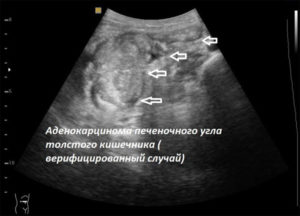

При обнаружении онкологического образования УЗИ помогает уточнить его локализацию, распространенность, наличие метастазов в печени и лимфоузлах. «Видит» ультразвук и опухоли, расположенные в параректальной клетчатке.

После хирургического лечения рака кишечника УЗИ делают для контроля послеоперационного поведения органа и раннего выявления рецидива.